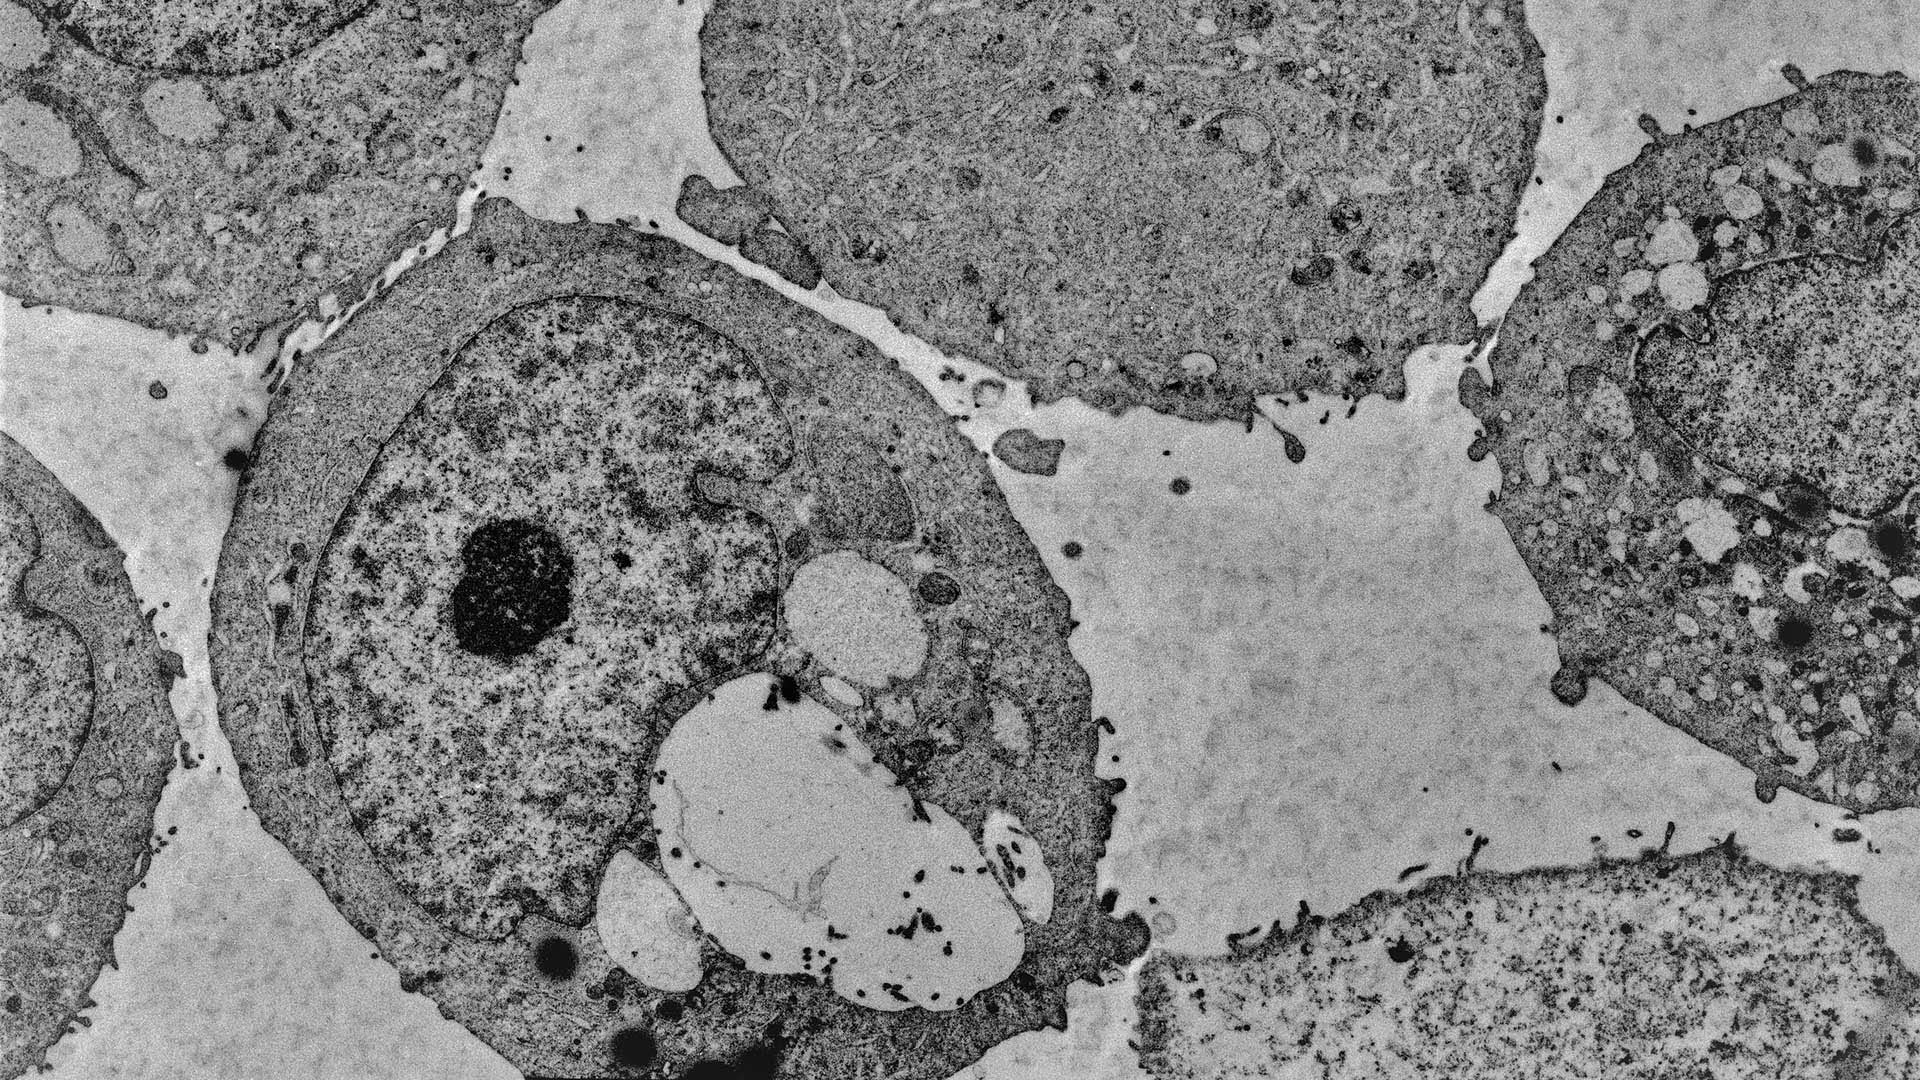

The Trotman lab developed RapidCaP in 2014. Since then, it has become an essential tool in prostate cancer research. The model has helped researchers uncover potential drug targets for prostate cancer, and develop new ways to predict whether tumors will become aggressive.